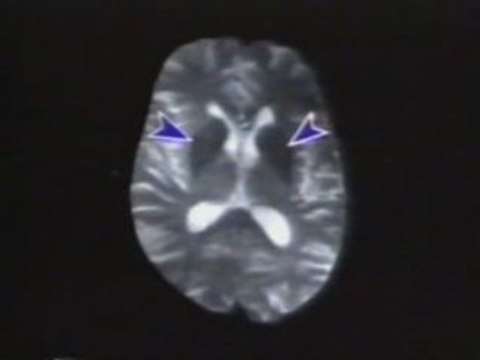

La investigación con células madre se ha convertido en una de las armas electorales de los demócratas ante las inminentes elecciones legislativas de EEUU. Un anuncio en el que Michael J. Fox apoya esta investigación y a una candidata demócrata ha suscitado fuertes críticas por los contrarios a las células madre embrionarias. Le acusan de exagerar los graves síntomas de Parkinson que muestra en el anuncio. Los demócratas están utilizando la promesa que plantea esta investigación como un arma electoral más contra los republicanos, ya de por sí 'heridos' por la guerra de Irak y los bajos niveles de popularidad de su presidente, George W. Bush. El pasado mes de julio, Bush utilizó por primera vez el veto presidencial para impedir que se ampliase la financiación federal de las investigaciones con células madre procedentes de embriones.